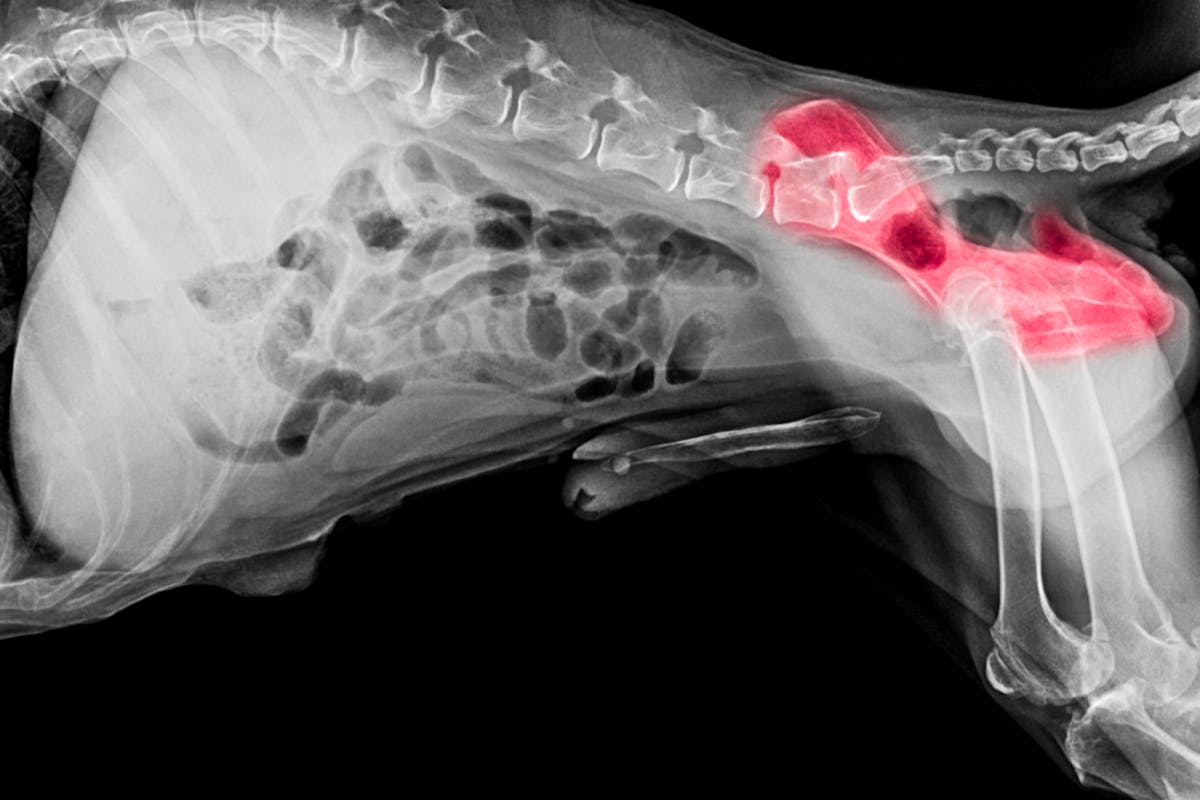

PennHIP is one screening method that measures the laxity of the hip joint using three different radiographic (x-ray) views or positions:

The distraction view and compression view are used to precisely measure:

The hip-extended view provides a supplementary assessment of the presence of osteoarthritis (OA) in the hip joint.

From assessment of the three images, dogs are given a distraction index (DI), which is a measurement of the laxity in the hip joint - the higher the number, the looser the hip joint. The individual dog’s DI can be compared to the overall breed average DI to aid breeders when making breeding decisions. Including dogs with a DI below the breed average in a breeding program helps shift the population in a lower-risk direction while still maintaining genetic diversity. DIs have shown a high level of heritability (although the figure varies between breeds).